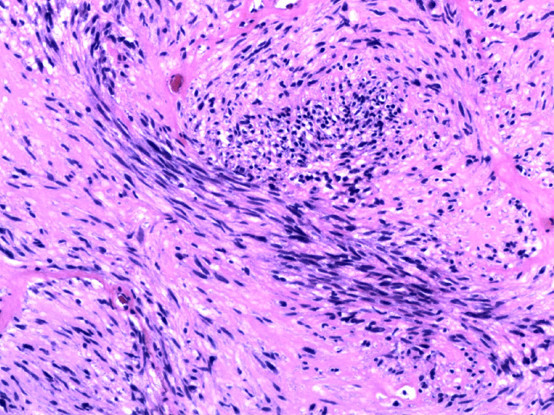

其实不是,因为影像学还处于形态学诊断阶段,目前它的分辨率还看不到细胞层次。而确诊指的是病理,在显微镜下看到肿瘤细胞才可做出最终判断。

打个比方,影像医生是“警察”,他要去确定犯罪嫌疑人,帮助内科外科医生抓到他,至于判断这个嫌疑人是不是真正的罪犯、如何量刑,则是要由法官来裁定的,而病理科的医生就是“法官”。

图片(老杨的病理切片图像)